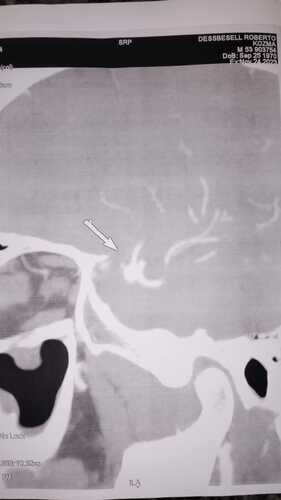

Eu Roberto Dessbesell 53 anos , motorista (caminheiro) na madrugada do dia 27 de julho de 2023 tive um AVC enquanto trabalhava (estava em viagem há Pelotas ) . Fui socorrido pelo atendimento médico do pedágio que me deu os primeiros socorros, fui levado para o hospital inconsciente e lá fiquei internado por 2 dias até que fui transferido ao Hospital de Panambi desde então estou em tratamento com neurologista e fisioterapia . Desde o AVC estou impossibilitado a trabalhar e fazer qualquer tipo de esforço físico pq esse aneurisma pode estourar a qualquer momento . Não podemos esperar pelo SUS pq o tempo para ser chamado é uma média inicial de 3 anos pra mais . E eu preciso fazer a cirurgia o mais rápido possível .

Recentemente tive que fazer novos exames e foi constato que preciso urgentemente fazer uma micro cirurgia na cabeça para retirada de um coágulo que se formou decorrente ao AVC.